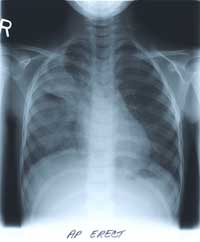

BELOW

is her CHEST X-RAY taken during the hospitalization.

Previous films from her NICU stay are not available.

Enlarge the CHEST X-RAY LEFT, enlarge the chest x-ray RIGHT.

WHAT ARE YOUR FINDINGS?